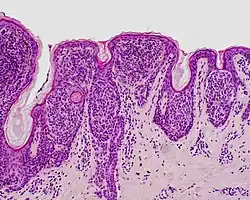

Compound nevus | Both the epidermis and dermis.[17] | ![]() |

ICD10: D22 (ILDS D22.L14) ICDO: 8760/0 | |